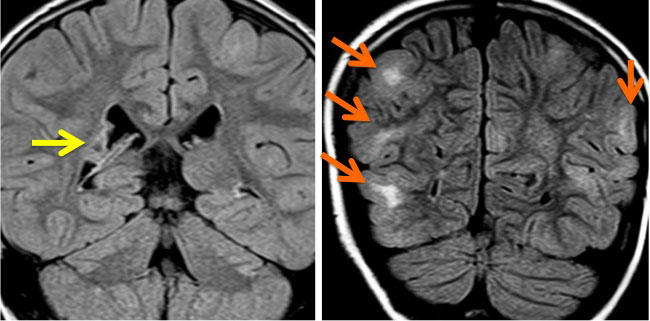

結節性硬化症 TSに見られる多発性上衣下結節 subependymal nodules

32歳で初めて睡眠時てんかん発症した患者さんのものです。側脳室壁だけに無数の上衣下結節がありますが,治療の必要はありません。SEGAではありません。

黄色の矢印で示すように脳室の壁に多数の小結節 (subependymal nodule SEN) があります。これらの結節はCTでは石灰化としてはっきり描出されますからCTの方が見やすいといえます。赤の矢印で示したのは,左前角 (caudothalamic groove) の腫瘍はSEGAですが,8年間観察してもほとんど増大しませんでした。でも今後に大きくなる可能性は否定できないものですから,これから何年も経過観察が必要です。

黄色の矢印は右の三角部のSEGAです。右の写真で大脳の皮質下白質が白くにじんで見える大脳皮質結節(cortical tubers) のも結節性硬化症の特徴です。このような病変がてんかん発作を生じます。